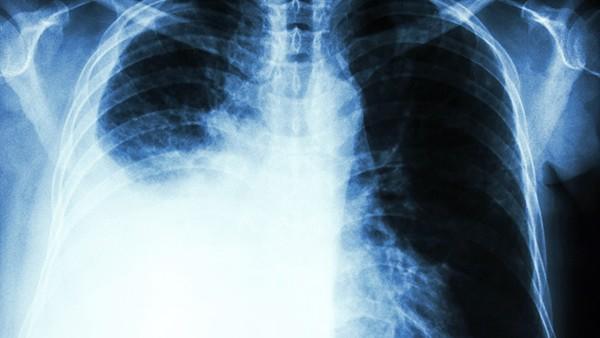

急性肺水肿(Acute Pulmonary Edema)是指肺部组织和肺泡内积聚过多的液体,导致气体交换障碍和呼吸困难。它是一种危急的医学情况,常常与心脏病(如心力衰竭)相关,但也可能由其他原因引起,如感染、创伤、高原反应等。及时有效的药物治疗对于控制急性肺水肿至关重要。